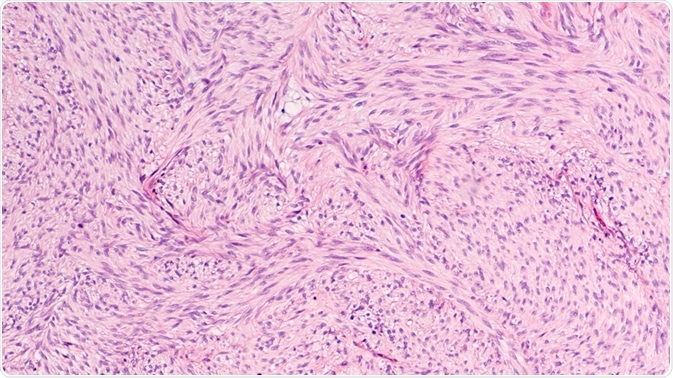

Stroma is the region of an organ or tissue that has a connective or structural role and is also comprised of all of the constituents that do not have a specific function within the organ, such as blood vessels, connective tissue, ducts, and nerves.

Connective tissues can be found within the stroma, with this essential tissue belonging to a group called: connective tissue proper.

The main function of this connective tissue proper is to fully secure the parenchymal tissue into place, which includes the nerves and blood vessels, to spread mechanical tension as to reduce any localized physical stress, and to bind the organs together. The stromal tissue mainly consists of an extracellular matrix that contains cells of connective tissue.